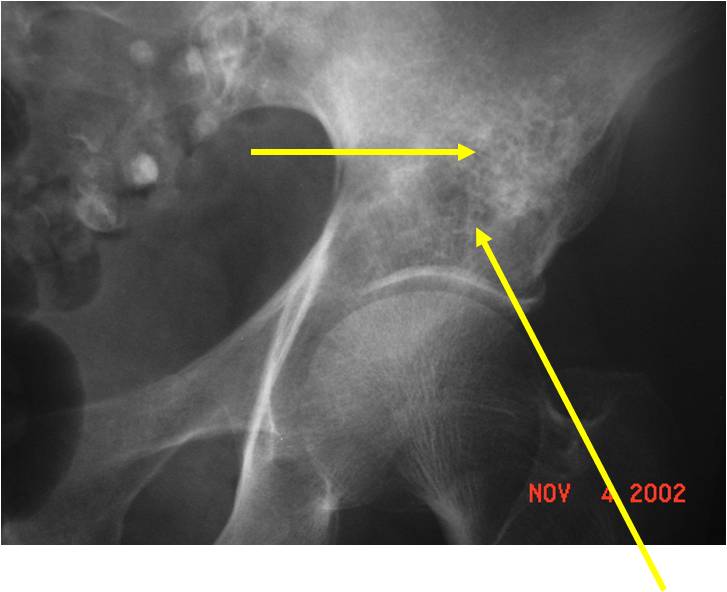

Radiology emulates pathology: Biphasic Tumor

- One region low grade chondrosarcoma

- Second more aggressive area with bone destruction, lysis of calcification, soft tissue mass

- Cortical permeation and a soft tissue mass in 70% of cases

Ill-defined, lytic intraosseous lesion

- Or extraosseous soft tissue mass

- Devoid of calcifications in continuity with lesions having the features of a cartilaginous tumor

Characteristically abrupt transition between chondroid tumor and dedifferentiated, lytic component

Bone may be expanded and adjacent cortex thickened

(Right Arrow)Aggressive Lytic Area (Dedifferentiated Sarcomatous Component) Cortical Destruction Soft Tissue Mass without Calcification